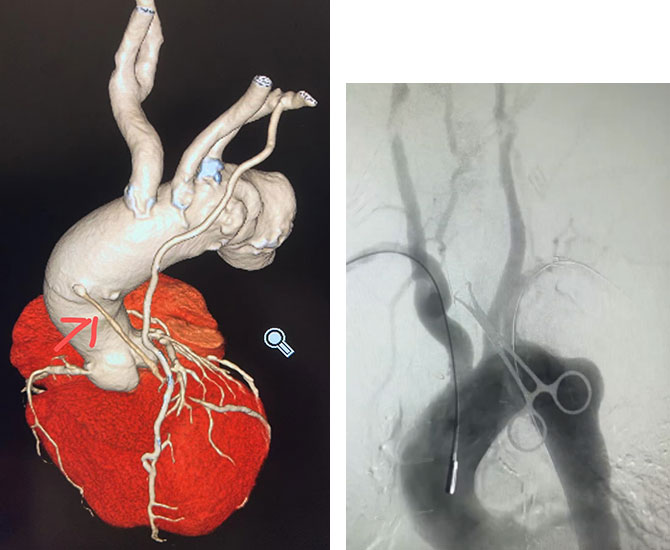

患者主动脉弓动脉瘤累及多个分支动脉

患者主动脉弓动脉瘤巨大,且累及多个分支动脉。主动脉腔内修复术(TEVAR)结合“烟囱”(平行支架技术)、“分支支架”、“原位开窗”等技术,均是微创手术治疗途径。然而“烟囱”技术容易产生内漏,不适合累及弓上多个分支血管的主动脉病变;“分支支架”“原位开窗”多在临床试验中。

经与患者、家属充分沟通,于5月17日为患者实施胸主动脉瘤覆膜支架腔内隔绝术+主动脉弓三分支原位开窗支架置入术。但因患者曾行冠脉搭桥术,术中保护桥血管血流,保障心脏血供,防止心脏缺血成为手术的难点。术中多学科默契配合,心外科指导冠脉桥血管定位,体循保障冠脉搭桥血管和脑部血管充分灌注,麻醉严密监控心脏和脑部功能配合,血管外科实施体内主动脉支架原位三开窗技术。手术成功,DSA造影提示:主动脉支架显影良好,贴壁正常,无名动脉、左颈总动脉、左锁骨下动脉支架通畅,未见支架内漏、移位,左锁骨下动脉桥血管通畅。术后经ICU严密观察心功能和神经体征,平稳度过围手术期,2天后顺利转回血管外科病房。经医护团队精心调整心功能,患者术后恢复良好并顺利出院。

手术后患者主动脉弓上分支血管血供良好